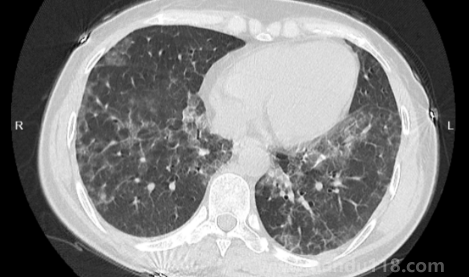

如何自查是否出現(xiàn)白肺(肺白了還能恢復(fù)嗎) 如何自查是否出現(xiàn)白肺(肺白了還能恢復(fù)嗎)白肺是目前很常見的情況,受新冠影響很多老年人都出現(xiàn)了白肺的情況,當(dāng)然也有年輕人會患上白肺。那么,如何自查是否出現(xiàn)白肺?平時怎樣保護自己的肺?一起來看看天都生活網(wǎng)... 小編 2023-01-06 874 #白肺